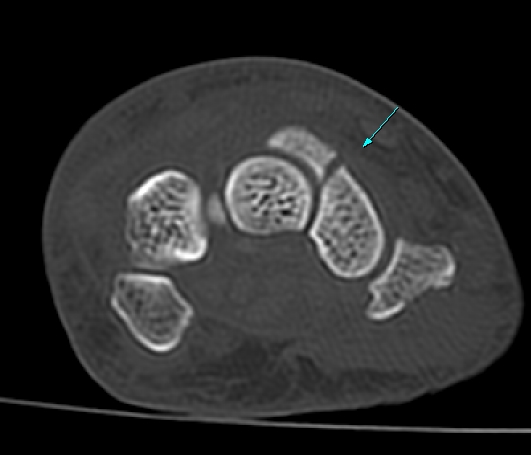

¼Õ¸ñ ¿ä°ñÃø ÁÖ»ó°ñ Á¾´Ü¸é °Ë»ç¿¡¼ ÁÖ»ó°ñ ÇÇÁú°ñ ¿¬¼Ó¼º ¼Ò½ÇÀÌ ¶Ñ·ÈÇÏ°í µ¿¹ÝµÈ ¿¬ºÎÁ¶Á÷ ºÎÁ¾ÀÌ °üÂûµÊ(»çÁø 3, 4)/

CT °Ë»ç